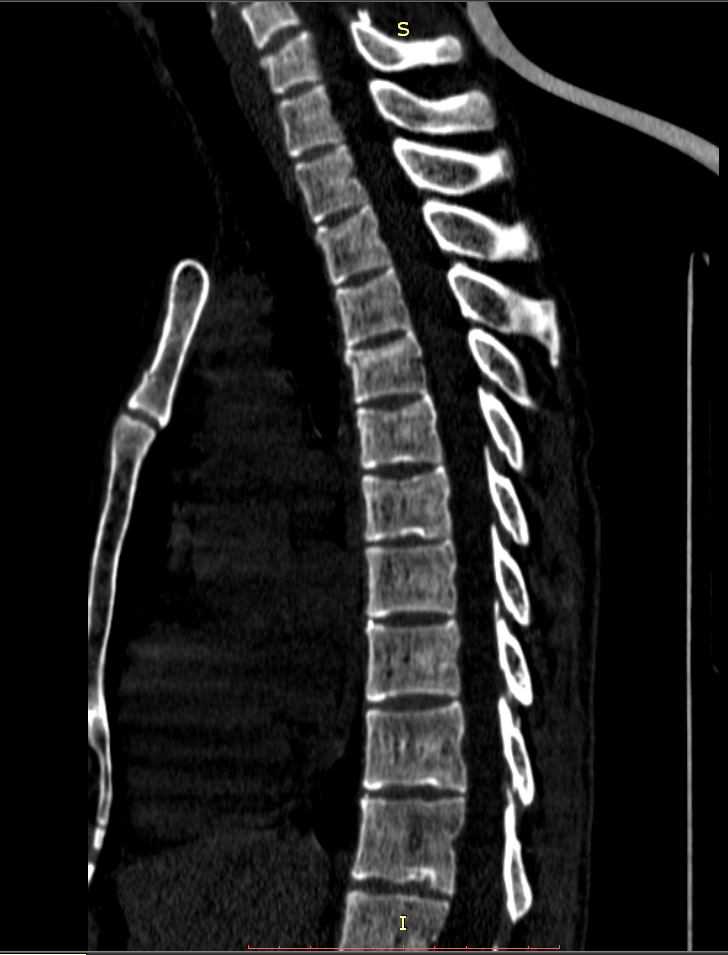

Здравствуйте! Меня сбил автомобиль. Бригада скорой помощи доставила меня в стационар с диагнозом - сотрясение мозга, ушиб грудного отдела позвоночника, компрессионный перелом грудного отдела позвоночника. При поступлении в стационар мне было сделано несколько рентгеновских снимков и поставлен диагноз - компрессионный перелом 4 грудного позвонка. Из-за "мутных" рентгеновских снимков через 9 дней мне сделали КТ и диагноз сняли на основании этого заключения.Судебная медицина - Прикрепленное изображение Мне сказали что перелом шейного позвонка у меня старый и поменяли диагноз - ушиб верхне-грудного отдела позвоночника, болевой синдром. По запросу я получила копию записи КТ. Всю запись КТ выложить не могу, т.к. не могу убрать фамилию. Выкладываю некоторые снимки: Судебная медицина - Прикрепленное изображение Судебная медицина - Прикрепленное изображение Судебная медицина - Прикрепленное изображение Судебная медицина - Прикрепленное изображение Судебная медицина - Прикрепленное изображение Судебная медицина - Прикрепленное изображение Судебная медицина - Прикрепленное изображение Действительно ли по этим снимкам можно сказать, что перелом шейного позвонка "старый"? Правильно ли описание КТ? Я не эксперт, но по-моему 5 грудной позвонок тоже поврежден. Можно ли оспорить заключение врача делавшего КТ? Если можно, то как это сделать? Ведь речь идет об установлении причинно-следственной связи между ДТП и травмой, а до ДТП у меня никаких травм позвоночника не было. Может рентгеновские снимки тоже о чем то скажут.Судебная медицина - Прикрепленное изображениеСудебная медицина - Прикрепленное изображениеСудебная медицина - Прикрепленное изображение

Для этого надо исследовать все сканы. Желательно - с 3D-реформацией изображения. С внимательным анализом костной структуры на уровне дефекта (есть ли признаки отека костной ткани в его зоне, наличие реакции мягких тканей, состояние краев фрагментов и т.д.). Получите все сканы КТ на диске или на флешке (они должны храниться в архиве КТ). И проконсультируйте их у высококвалифицированного специалиста по КТ и/или в любом крупном Бюро судебно-медицинской экспертизе, в штате которого есть эксперт-рентгенолог. Возможно, понадобится сделать контрольное КТ исследование с целью обнаружения динамики выявленных изменений (впрочем, вопрос об этом будет решен после ознакомления рентгенолога с КТ, т.к., возможно, доп.исследование не будет необходимо или же более целесообразным окажется иной вариант лучевой диагностики). По результатам консультации станет понятно, есть ли реальные основания для заявления мотивированного ходатайства о назначении дополнительной или повторной экспертизы (как это сделать - подскажет Ваш адвокат).